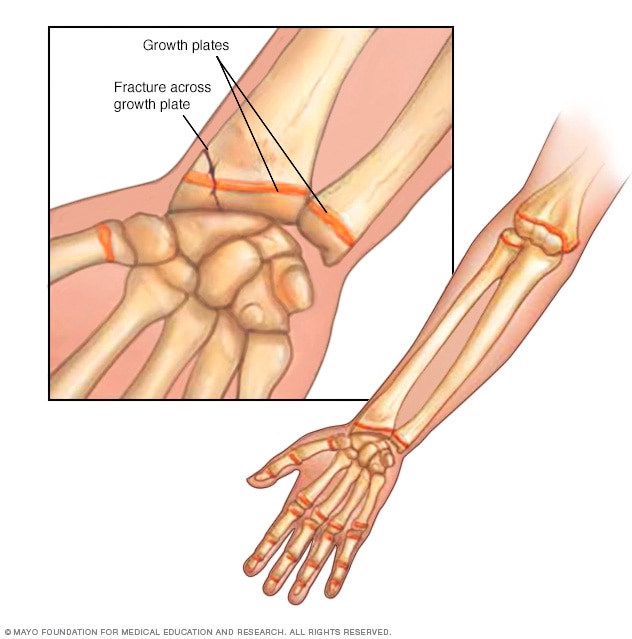

Growth plate fracture

Growth plates are located near the ends of your child's bones. If a fracture goes through a growth plate, it can result in a shorter or crooked limb.

A growth plate fracture affects the layer of growing tissue near the ends of a child's bones. Growth plates are the softest and weakest sections of the skeleton — sometimes even weaker than surrounding ligaments and tendons. An injury that might cause a joint sprain for an adult can cause a growth plate fracture in a child.

Growth plate fractures often need immediate treatment because they can affect how the bone will grow. An improperly treated growth plate fracture could result in a fractured bone ending up more crooked or shorter than its opposite limb. With proper treatment, most growth plate fractures heal without complications.